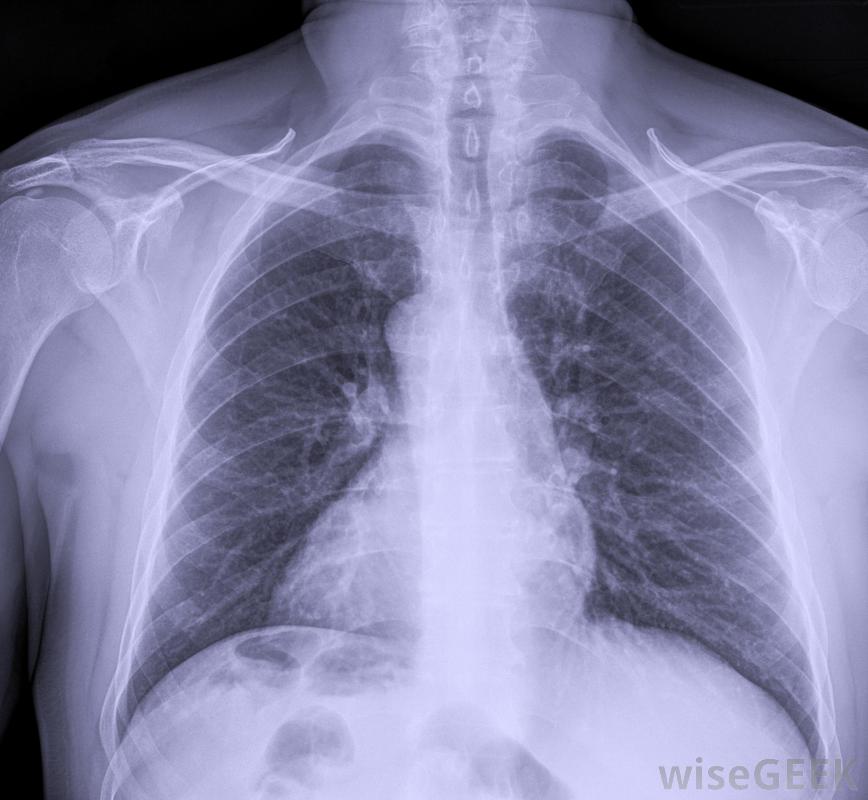

也可以进行胸部X光检查,以寻找睾丸肿瘤扩散的迹象有时病人在睾丸肿瘤扩散后才会去看医生,这会导致身体其他部位出现恶性肿瘤。肿瘤扩散的过程称为转移,新的肿瘤在身体不同部位的生长称为转移瘤。根据转移灶的位置不同,症状可能包括咳嗽、呼吸困难、恶心、食欲不振、背痛或颈部肿块。有些肿瘤分泌激素,会导致乳房肿胀,一种被称为女性乳房发育症的疾病。

睾丸肿瘤可以通过放疗和化疗来治疗睾丸肿瘤的诊断通常是通过超声扫描来确定的。然后对骨盆和腹部进行胸部X光和CT扫描,以发现任何扩散的迹象。睾丸肿瘤的治疗通常包括手术切除受影响的睾丸,以及附近的淋巴结。取决于肿瘤的类型和扩散的距离,手术后可进行放疗或化疗。